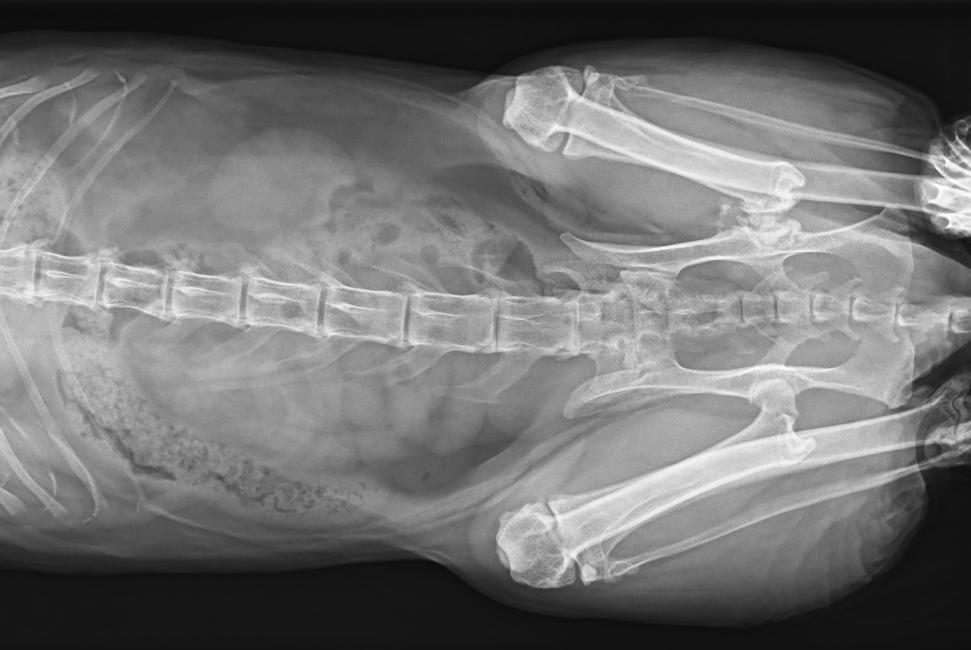

● 17*17大尺寸平板探測器,獲得高質(zhì)量圖像

● 優(yōu)異的空間分辨率及信噪比,提升圖像質(zhì)量

● 采用線(xiàn)噪聲消除技術(shù),使成像質(zhì)量提升40%

● 智能高效的圖像處理軟件,大幅提升圖像質(zhì)量

● 可浮動(dòng)床面設計,滿(mǎn)足大部分中小型寵物檢查